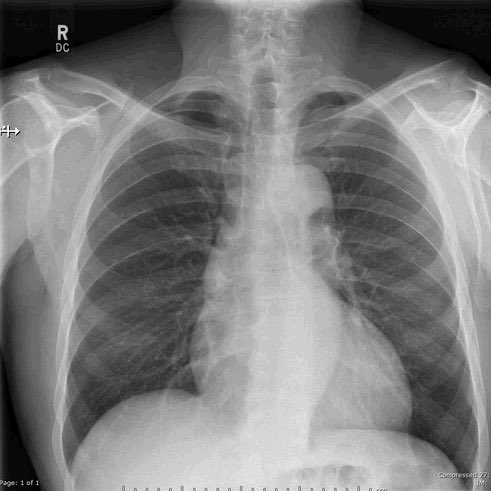

٤-هذه صورة للرئة الطبيعية قبل الالتهاب وصورة بعد دخول الرئة في متلازمة الضائقة التنفسية الحادة ARDS (هذا البياض الشديد عبارة عن التهاب حاد) ويصعب تبادل الغازات التنفسية وتصبح متصلبة ولاتستطيع العمل ومن ثم يتم وضع المريض علىً جهاز تنفسي ..